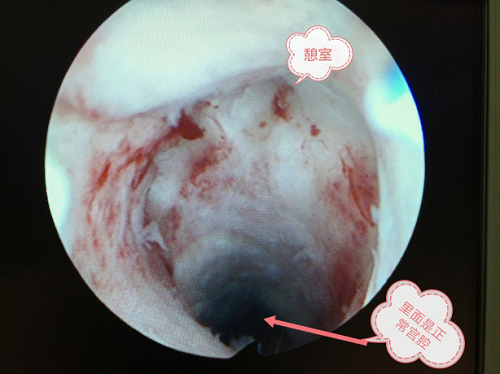

在过去几十年,众多因素导致了大量的剖宫产分娩,这些产妇的子宫都叫瘢痕子宫。随着二孩政策的开放,这些瘢痕子宫有机会再次孕育胚胎。瘢痕子宫如果切口愈合不良就会出现瘢痕憩室,使原本规则的子宫腔变成“一室一厅“,如图一、二所示。胚胎如果在“门厅”安家,也就是种植在瘢痕憩室的位置就形成剖宫产后子宫瘢痕处妊娠,如图三所示。

如果把瘢痕妊娠作为普通宫内妊娠一样对待,终止妊娠的方式采用药物流产或人工吸宫流产大概率会导致比较严重的后果。应该怎么处理呢?首先要去实力雄厚、医生经验丰富的综合性公立大医院。这样能保证瘢痕妊娠被正确识别和诊断,后续得到恰当处理,一旦处于危险的状况时有足够的抢救能力。山东省立医院妇科采用宫腔镜监护下瘢痕妊娠胚物清除术治疗早期的瘢痕妊娠,成功治愈百例左右的患者。该方法用宫腔镜定位胚胎位置,用垂体后叶素暂时收缩血管减少子宫血供,吸引宫腔后再次宫腔镜检查及处理可能的残留,真正实现“可视人流”,保证流产的完全性。手术一般在半小时内完成,安全快捷。